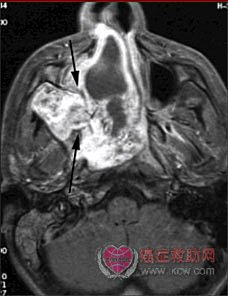

本病多起源于鼻咽顶部的纤维组织及血管组织,肿瘤中血管丰富,血管壁薄,为单层上皮,其下为平滑肌,缺乏弹性组织,损伤后不易收缩,常引起大出血。肿瘤增长时可压迫邻近骨壁,侵入鼻窦、眼眶、鼻腭窝,甚至破坏颅底进入颅腔。因此,此病在组织学上虽属良性,但在临床上可引起严重后果。

较大的肿瘤通常呈双叶型或哑铃型,其中一部分瘤体填充在鼻咽而另一部分则延伸至翼腭窝。

大型瘤体